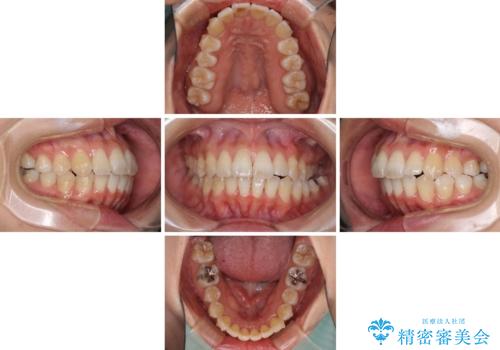

- 上下の歯の前後関係が乱れ、歯に負担がかかるとのことで来院された患者様です。

下顎が右左側に変位しているため、左側奥歯の咬み合わせが上下反対の関係となっていました。

また、上下ともに歯列が狭窄しており、奥歯以外にも反対咬合が認められました。

歯列全体の拡大と、歯と歯の間を削ることでスペースを獲得し、インビザラインによる矯正治療を行うこととしました。